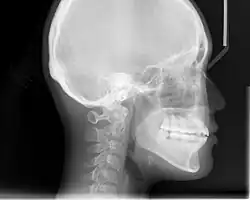

In the postwar period, cephalometric radiography[14] started to be used by orthodontists for measuring changes in tooth and jaw position caused by growth and treatment.[15] The x-rays showed that many Class II and III malocclusions were due to improper jaw relations as opposed to misaligned teeth. It became evident that orthodontic therapy could adjust mandibular development, leading to the formation of functional jaw orthopedics in Europe and extraoral force measures in the US. These days, both functional appliances and extraoral devices are applied around the globe with the aim of amending growth patterns and forms. Consequently, pursuing true, or at least improved, jaw relationships had become the main objective of treatment by the mid-20th century.[8]